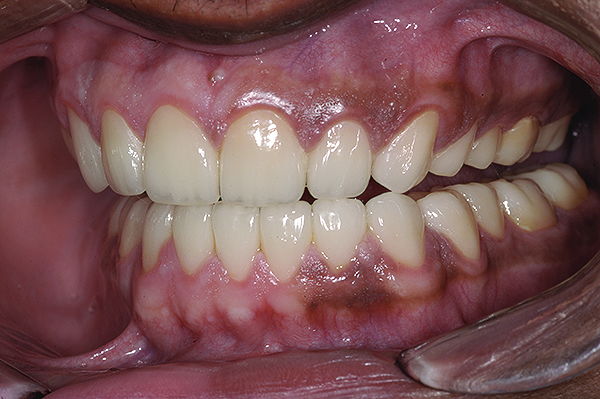

The final restorations depicted restoration of form, function, and beauty, with good harmony of restoration and the periodontium (Figure 19 through Figure 25). MIP was in harmony with CR, and right and left lateral excursion discluded all posteriors with anterior group function. The postoperative orthopantomogram (OPG) (Figure 26) shows the treatment done while maintaining the vitality of anterior teeth.

Figure 24. Final restoration with mandible in right lateral excursion.

Figure 24

Figure 25. Final restoration with mandible in left lateral excursion.

Figure 25